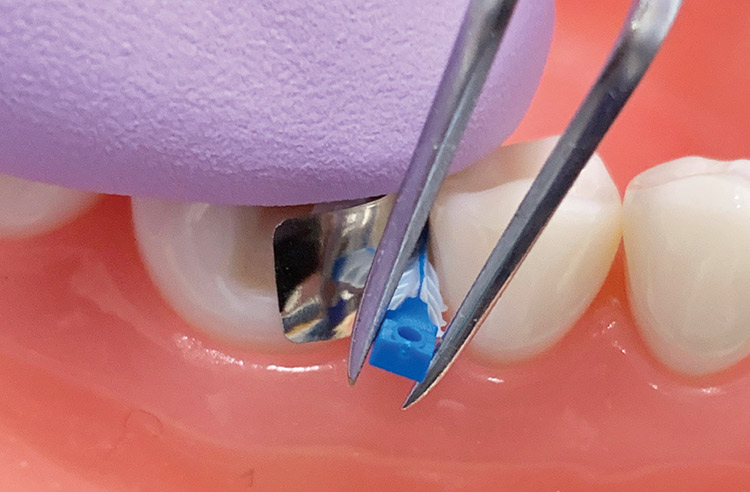

フュージョン ウェッジは、下部鼓形空隙の大きさに合ったものを選択し、ピンセットで把持しながら下部鼓形空隙に挿入する(図6)。ウェッジの上下の方向を確認し、フュージョン バンドを軽く指で保持しズレないように注意しながら、ウェッジをしっかりと挿入する(図7)。

図6 バンドを軽く指で保持しながら、フュージョン ウェッジ スモール(ブルー)をピンセットで把持し下部鼓形空隙に挿入。

図7 ウェッジをしっかりと挿入。